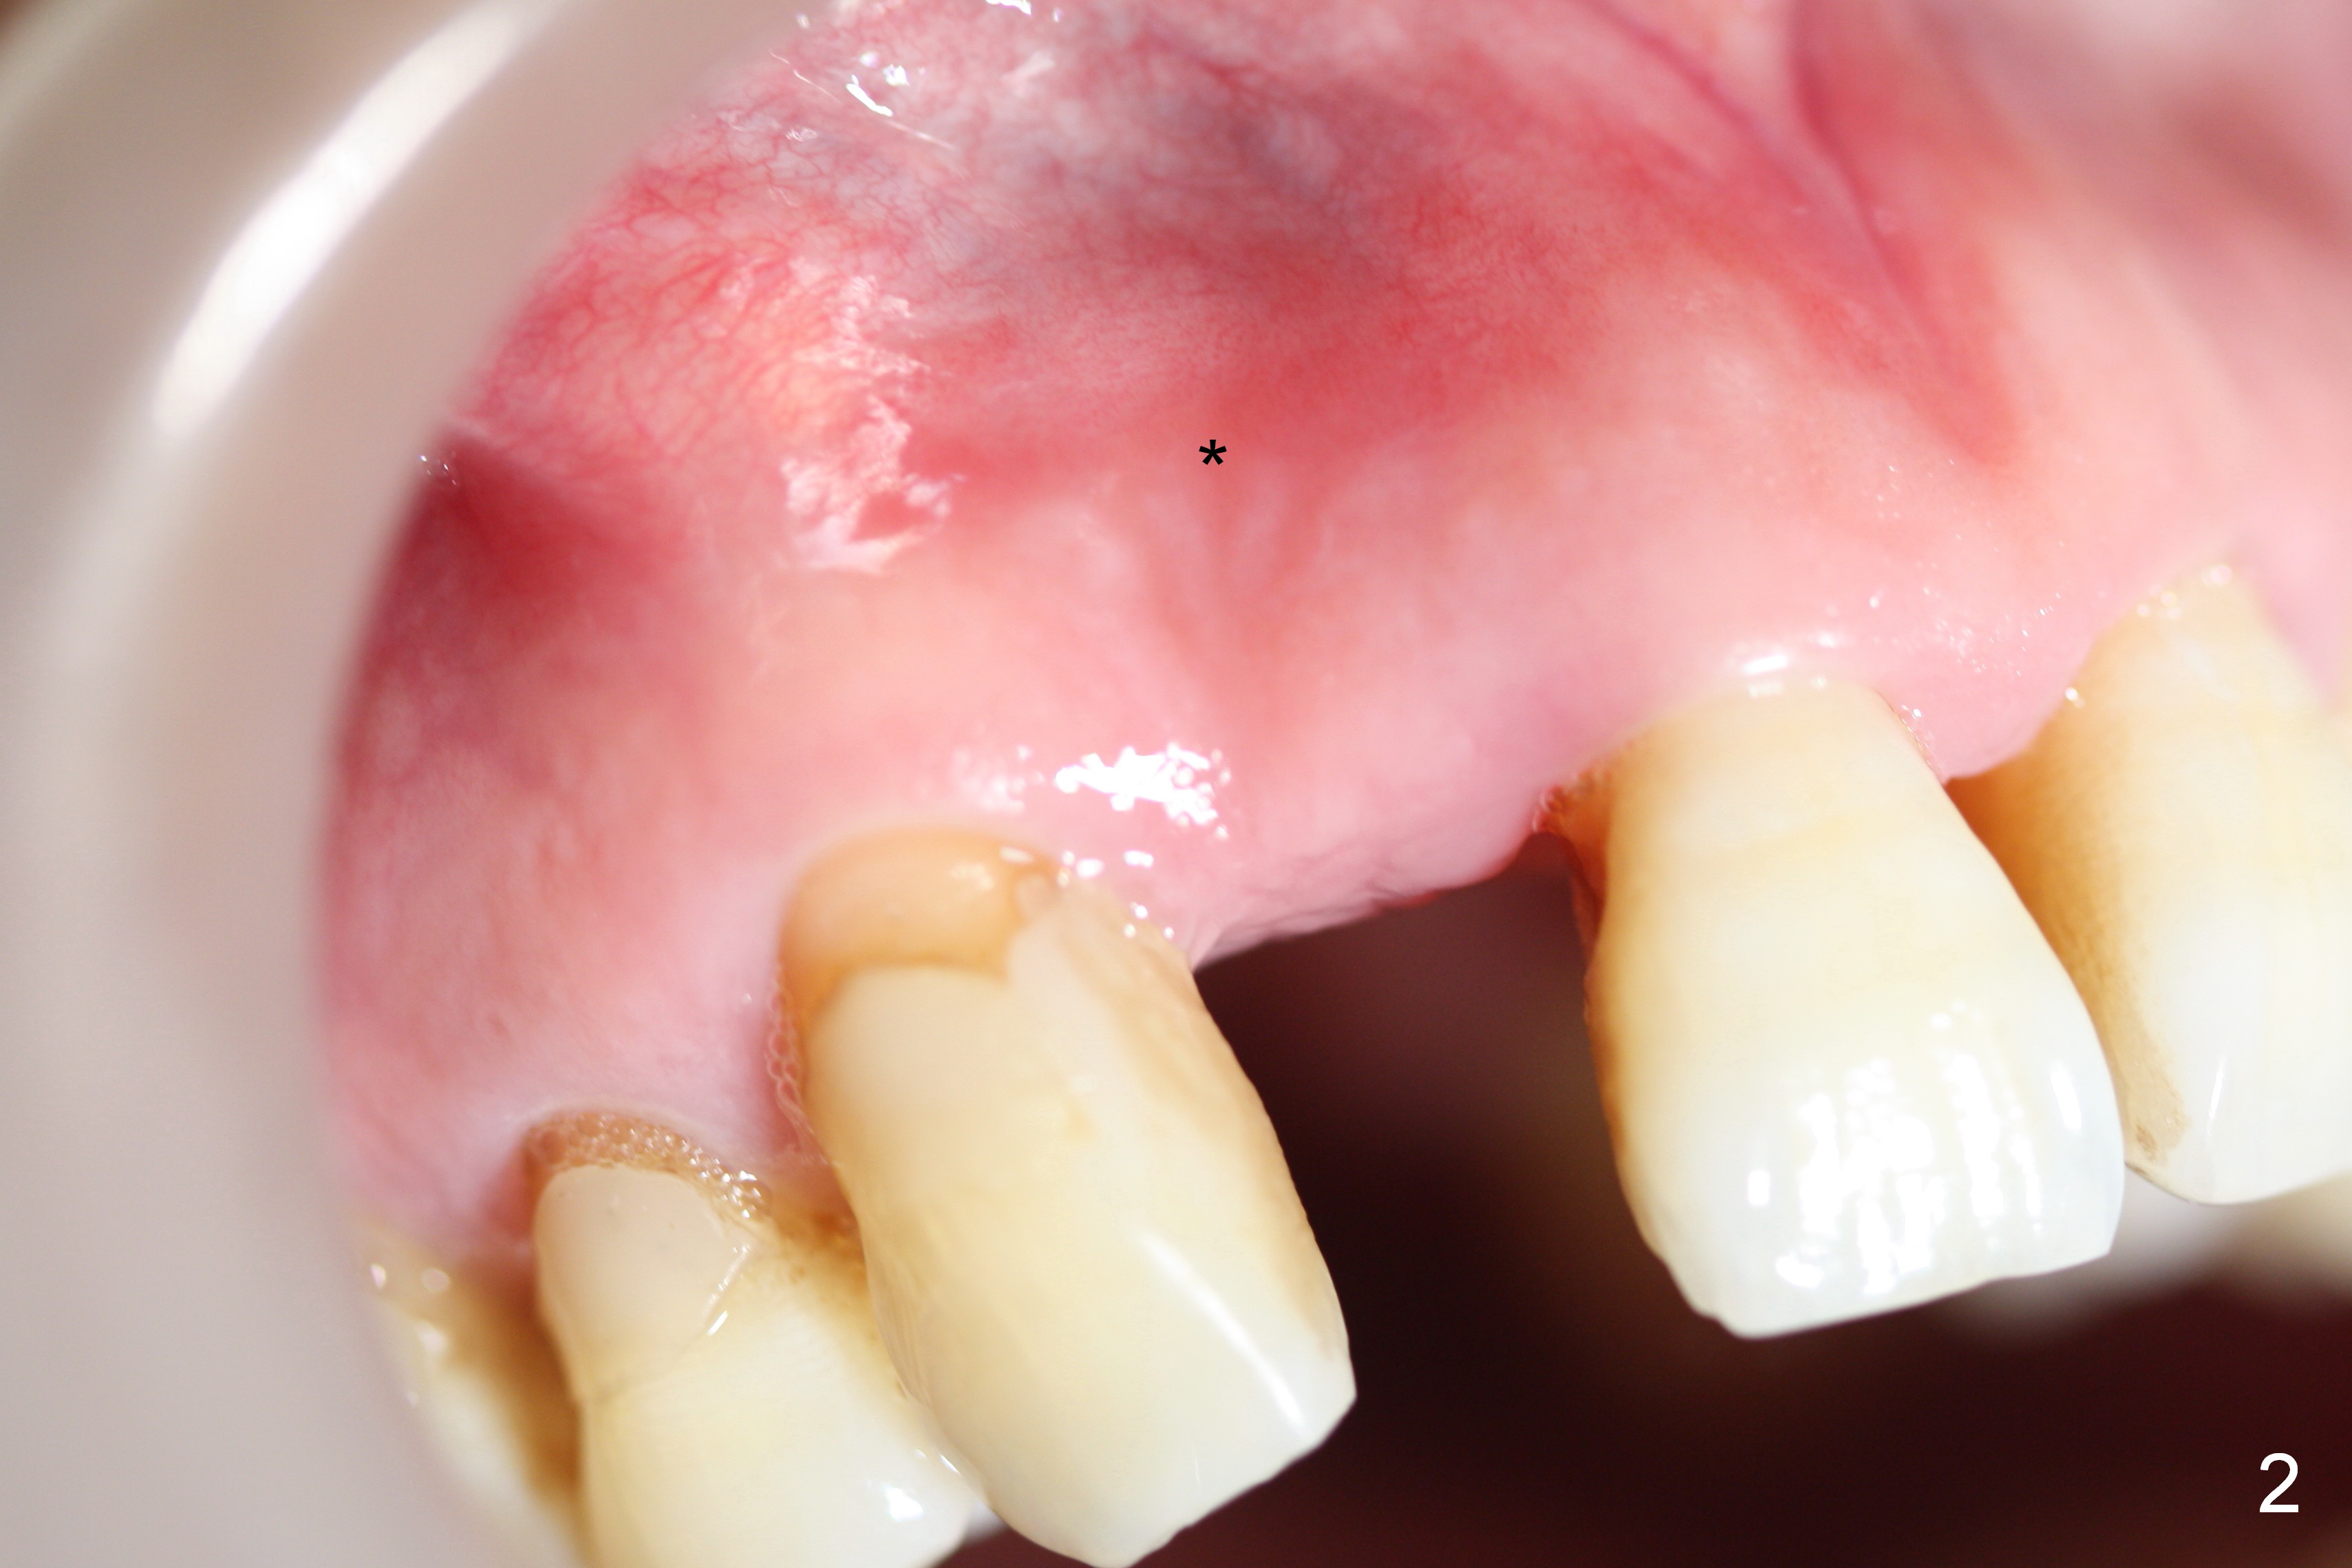

Preop exam shows the apparent wide ridge at #7 (Fig.1). What is ignored preop is the concavity in the apical buccal region (Fig.2 *). When a 3x16(4) mm 1-piece implant is being placed (Fig.3 *, flapless), the apical buccal plate vibration is felt. The biggest mistake is that initial osteotomy is ~ 6 mm shy of the implant length, partially because of 6 mm gingival height. Since the tooth #6 is symptomatic after RCT with paste overfill (Fig.4 >), apicoectomy is contemplated at #6 with exploration of the buccal plate at #7 (Fig.5). Since the implant appears to be long enough, implant apical resection is performed (Fig.6). Since there is coronal thread exposure due to previous periodontitis (Fig.7 <), bone graft is placed in these 3 defective areas after decortication.

Extending the initial osteotomy to the full length of the implant is critical. If perforation is detected early, the trajectory can be changed. Incision should be made if there is no CBCT study. The incision heals 1 and 4 weeks postop (Fig.8,9). The patient returns for final restoration 6 months postop. Apical defects appear to have healed at #6 and 7 (Fig.10,11). Fig.12 is taken 11 months postop and 5 months post cementation. The patient has an accident 9 months post cementation. In fact the implant is alright, while the tooth #6 fractures and #8 subluxates.